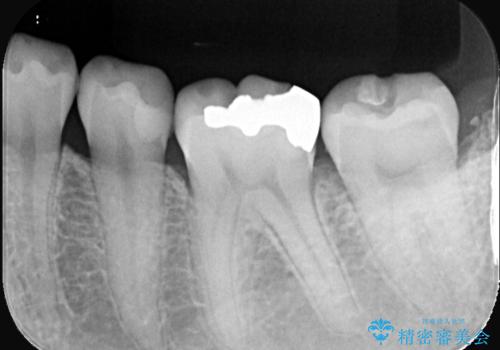

- 初診時にお口の中をチェックしたところ虫歯があり、大きさから部分的な詰め物のお話をしました。材料の特性を説明し、再び虫歯になりにくいセラミックインレーを選択されました。

セラミックインレー接着時にはラバーダム防湿を行いました。